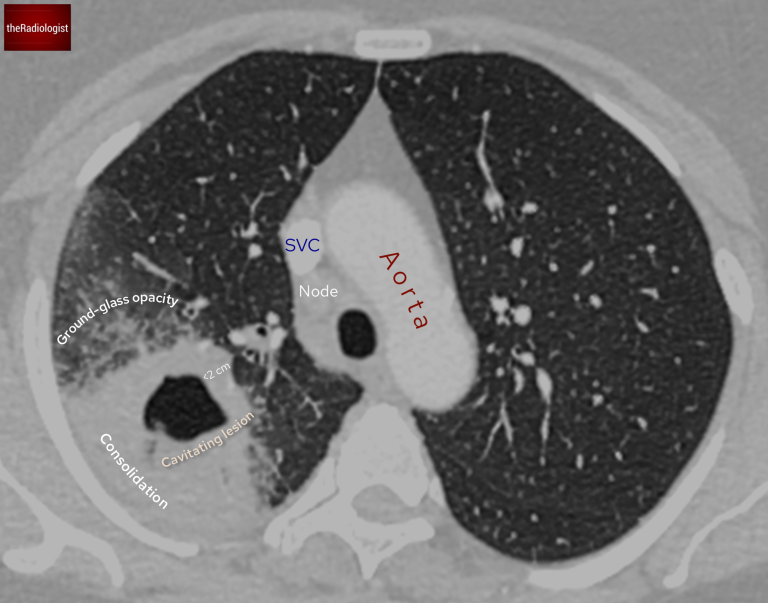

A CT scan provided further clarity:

• The lesion’s wall thickness was measured at less than 2 cm.

• Surrounding ground-glass opacity and consolidation were noted.

• The right paratracheal lymph node enlargement seen on X-ray was confirmed.

The wall of the cavitating lesion measures at less than 2 cm and there is surrounding consolidation and groundglass opacity.